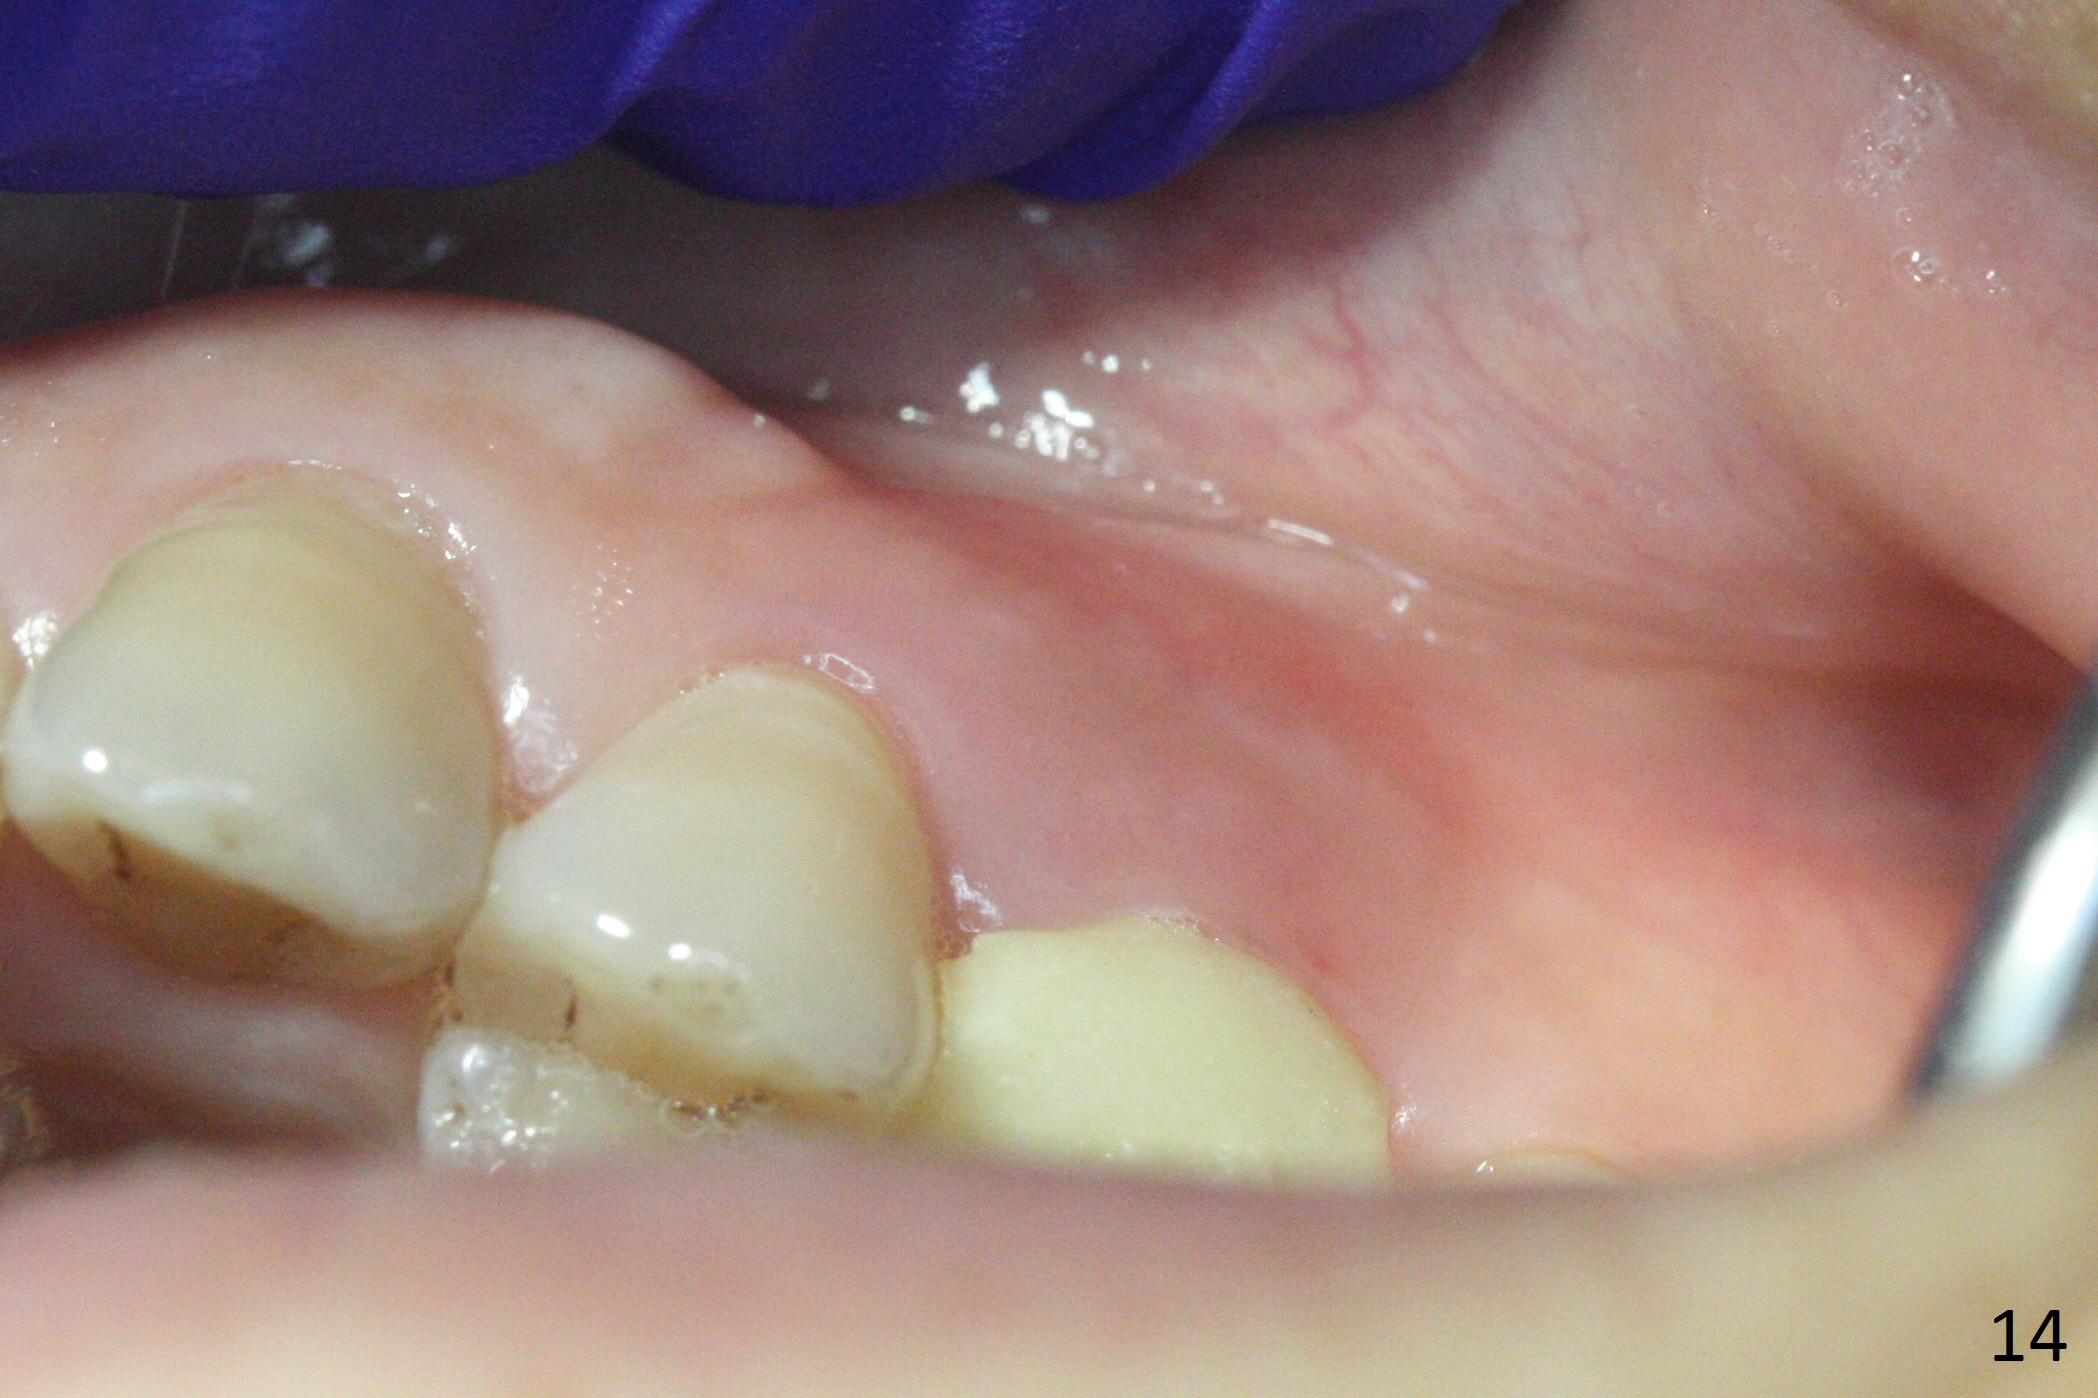

The buccal gingival inflammation subsides 1 week postop (Fig.13,14). There is no bone loss 4 months postop (Fig.15,16). The crown is recemented 6 months post cementation (probably due to short abutment); there is a residual cement (Fig.17 <), which is removed (Fig.18).